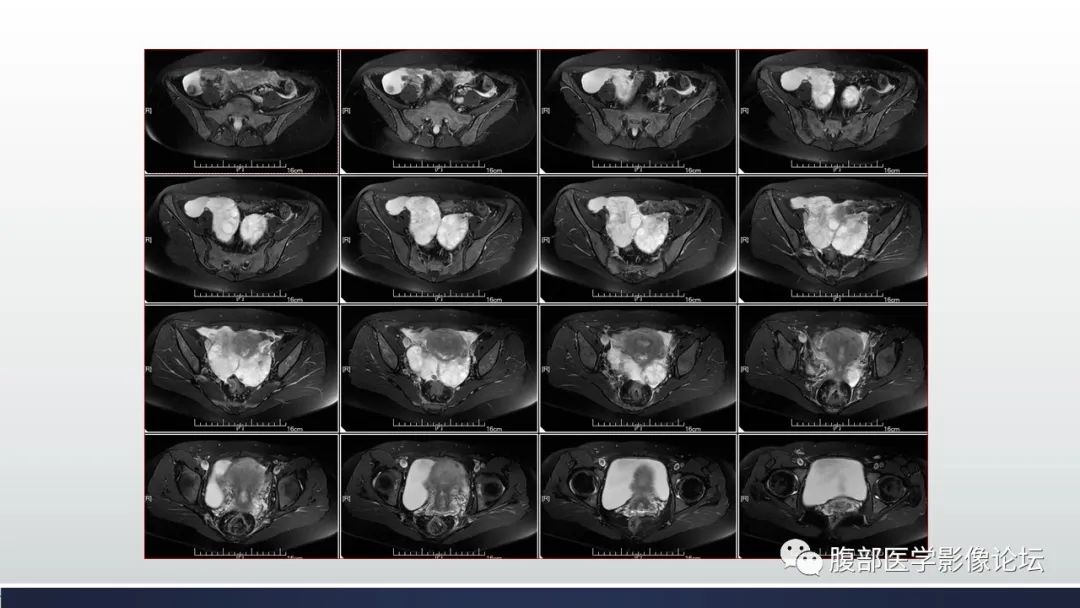

【病例】子宫内膜透明细胞癌1例MR-1

【病例】子宫内膜透明细胞癌1例MR-2